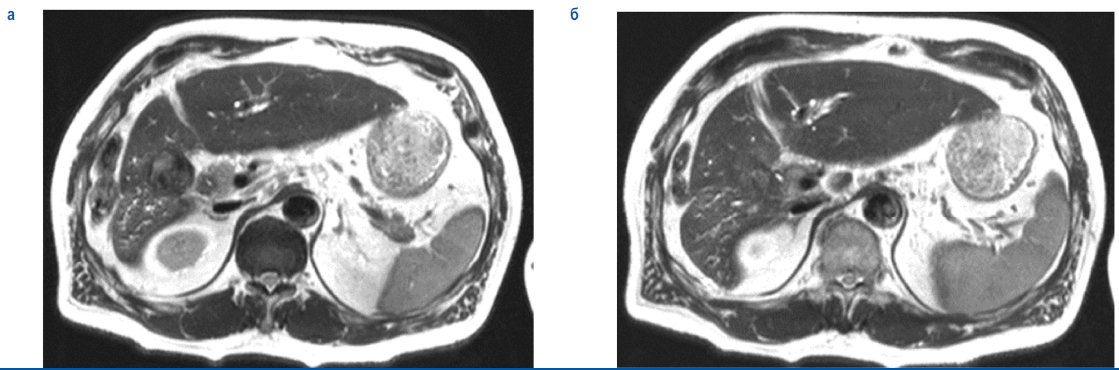

По данным магнино-резонансной томографии (МРТ) ОБП – формальная МР-картина опухоли Клатскина с распространением на пузырный проток и желчный пузырь. Метастатическое поражение лимфатических узлов брыжейки и печеночно-двенадцатиперстной связки (рис. 2, 3).

Рис. 2. Изображение магнитно-резонансной томографии – опухоль ворот печени.

Fig. 2. MRI scan – hilar cholangiocarcinoma.

Рис. 3. Изображение магнитно-резонансной томографии – опухоль ворот печени.

Fig. 3. MRI scan – hilar cholangiocarcinoma.